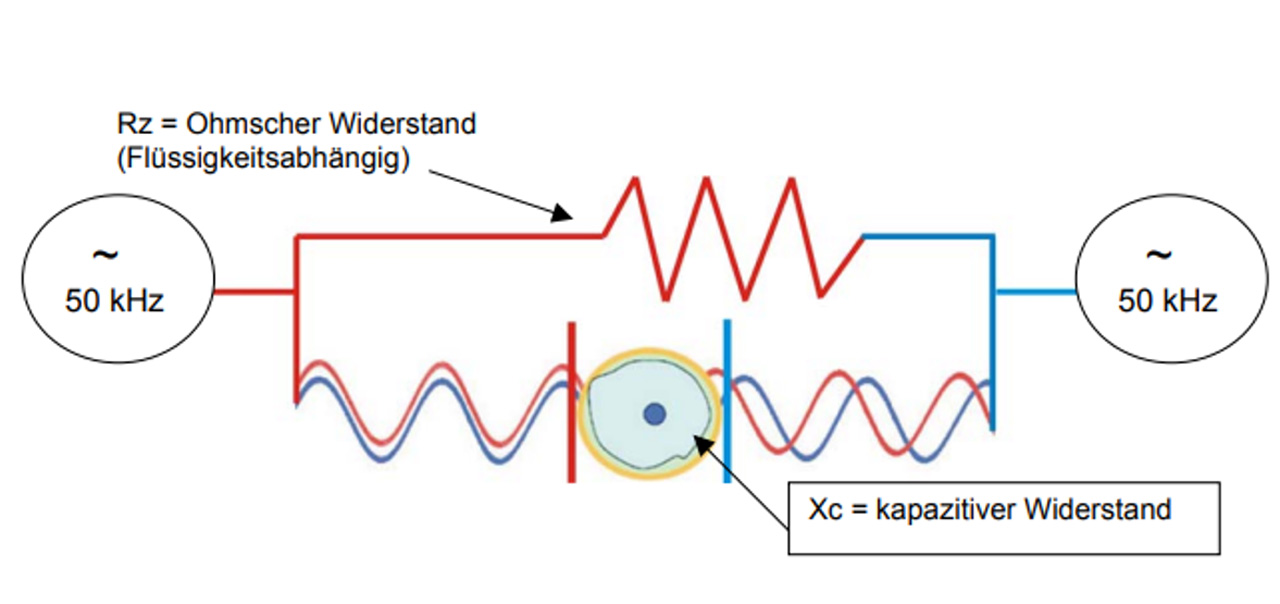

Die BIA basiert auf der Messung spezifischer Leitfähigkeiten bzw. spezifischer Widerstände (Impedanz) von Körpergeweben, indem ein sehr schwacher Wechselstrom durch den Körper (800 µA, 50 kHz) auf verschiedenen Wegen geleitet wird.

Exkurs: kapazitiver Widerstand

Zellen haben eine geladene Zellmembran und wirken als Kondensator. Der Kondensator (die Zelle) wird im Wechselstrom ständig geladen wieder entladen. Das braucht eine gewisse Zeit, so dass der Wechselstrom „gebremst“ wird. Man spricht vom kapazitiven Widerstand, der ist bei 50 kHz am höchsten. Fettzellen haben nur einen minimalen kapazitiven Widerstand und werden daher nicht erfasst.